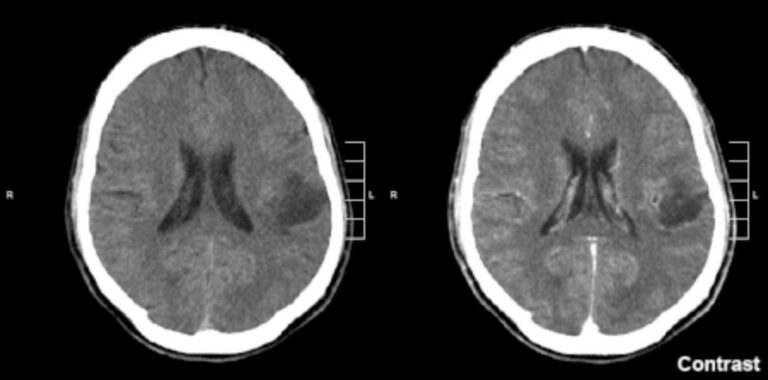

Os meningiomas são tumores que se originam das meninges, as membranas que envolvem o cérebro e a medula espinhal. Embora a…